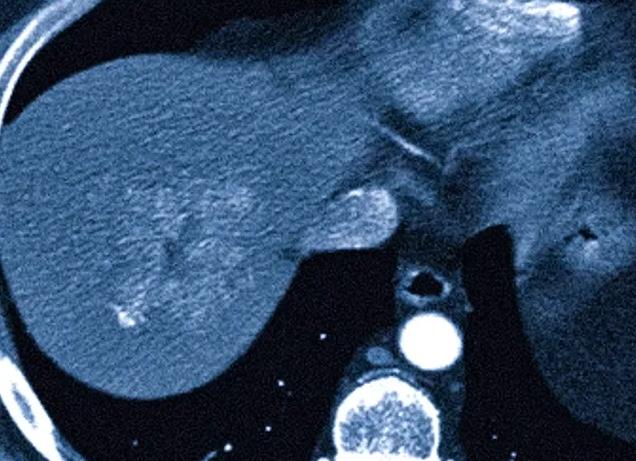

Гормональным сбоем у женщины называется результат воздействия на организм различных факторов, который приводит к нарушению работы гормональной системы на разных ее уровнях. К внешним причинам патологии относятся физические и психологические нагрузки (атмосфера в семейной и профессиональной жизни). К внутренним — состояние здоровья (хронические заболевания ). Определить гормональный сбой у женщины можно с помощью анализа крови.